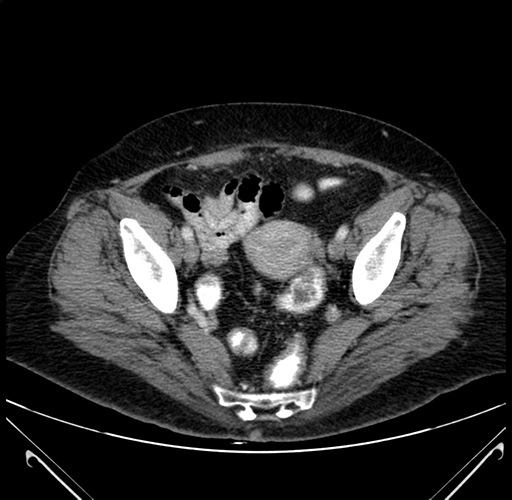

Pre-Chemo: Axial Venous

Axial Venous